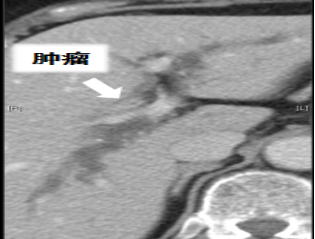

患者病史:80岁女性,两周前无明显诱因出现皮肤、巩膜黄染,伴皮肤瘙痒。上腹部CT示肝门部胆管占位伴肝内胆管扩张。2006年因“心绞痛”于外院行“冠脉支架置入术”

病灶评估:通过计算机辅助手术规划系统进行了三维重建,绿色为胆管系统,黄色为肿瘤病灶,红色为主动脉系统。术前诊断:肝门部胆管癌(IV型) |

病情特点:病灶主要位于左右肝管汇合部,偏向左侧。患者存在胆管变异,右前、右后肝管不相通,右前胆管汇入左肝管,B4和左外肝管不相通。